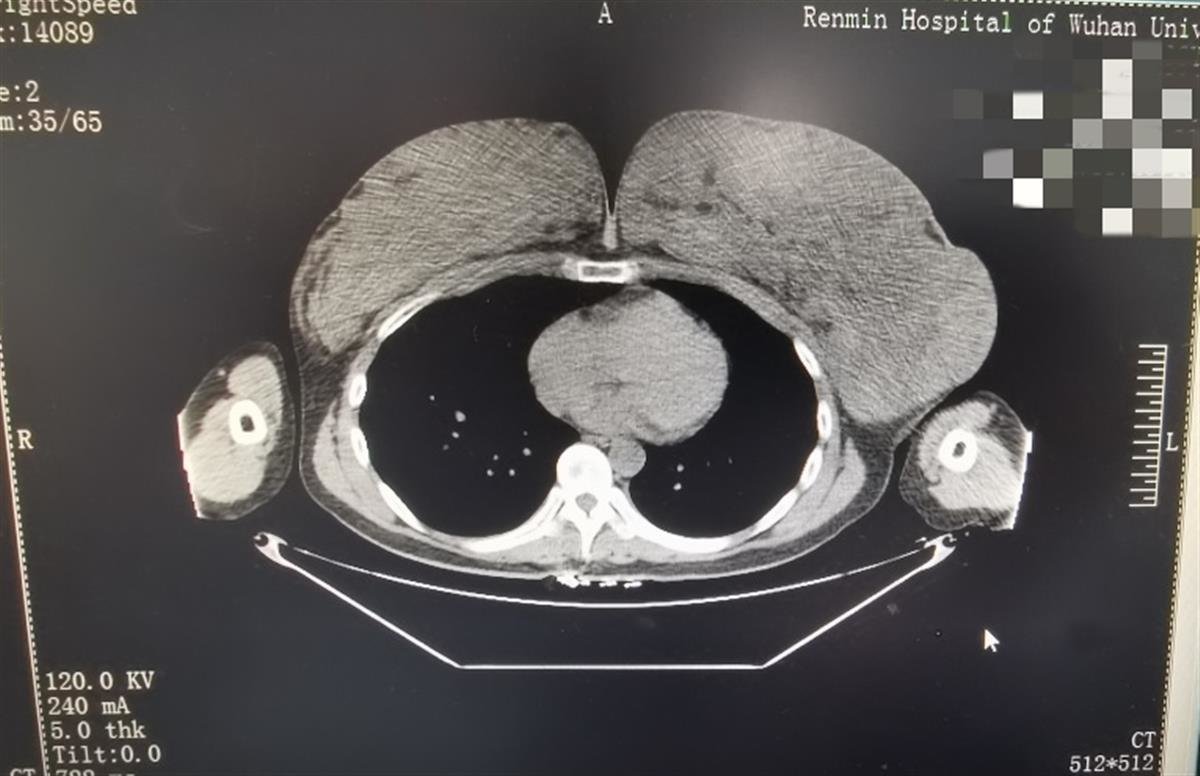

巨乳症,也被称为乳房肥大症,是指乳房的体积和重量超过正常限度的情况。

如果一侧乳房的体积超过400ml或者乳房的重量超过人体重的3%,就可以定义为巨乳症。

巨乳症患者的乳房外观显著大于正常女性的乳房。